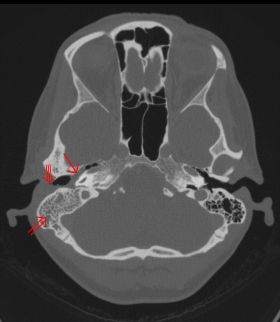

꼭지돌기염의 진단은 기본적으로 병력 청취와 신체 검사를 통해 임상적으로 이루어진다. 영상 검사는 진단에 추가적인 정보를 제공하는데, 진단의 표준 방법은 MRI 스캔이지만 CT 스캔이 더 흔하게 사용된다. CT 스캔은 뇌와 안면 신경 손상 위험 정도를 확인하는 데 더 선명하고 유용한 이미지를 제공하기 때문이다. 평면(2차원) X-ray는 진단적 유용성이 상대적으로 떨어진다. 만약 귀에서 고름과 같은 분비물(배액)이 나온다면, 원인균을 확인하기 위해 미생물 배양 검사를 시행할 수 있다. 하지만 환자가 이미 항생제를 복용하기 시작했다면 검사 결과가 음성으로 나올 수도 있다. 탐색 수술은 꼭지돌기와 주변 부위를 직접 확인하기 위한 최후의 수단으로 고려될 수 있다.